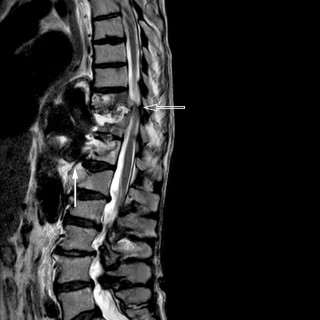

Magesmerter hos barn er en hyppig årsak til henvisning til barnemedisinsk og kirurgisk spesialisthelsetjeneste. Akutt appendisitt, obstipasjon og gastroøsofageal refluks er blant de vanligste diagnosene. Ofte kan barn ha diffuse symptomer, og selv om «det vanligste er det vanligste», er det viktig å være oppmerksom på symptomer som tyder på alvorlig, underliggende patologi. Tett samarbeid mellom fastlege, barnelege, barnekirurg og radiolog kan være viktig for å komme til målet. En jente tidlig i tenårene hadde vært plaget av «treg mage» siden småbarnsalder og hadde gjennom de siste fem årene...